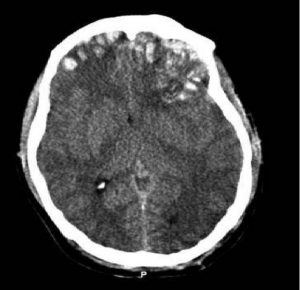

Traumatic brain injuries can be classified into mild, moderate or severe categories, depending on the extent of damage to the brain. Mild TBIs, often referred to as concussions, might involve temporary loss of consciousness or confusion. Moderate to severe TBIs, however, can lead to long-term physical, cognitive or emotional impairments. Each injury is unique, with the outcomes depending on factors such as the location and severity of the injury, the patient’s age and health and the speed and quality of medical intervention.

Immediately after a TBI, the priority is stabilizing the patient and preventing further damage. Emergency medical care may include surgery to relieve pressure on the brain, controlling bleeding, or removing damaged tissue. In more severe cases, patients may be placed in an induced coma to reduce brain activity and allow healing. This stage is critical to survival. Swift, skilled medical intervention can significantly influence long-term outcomes.